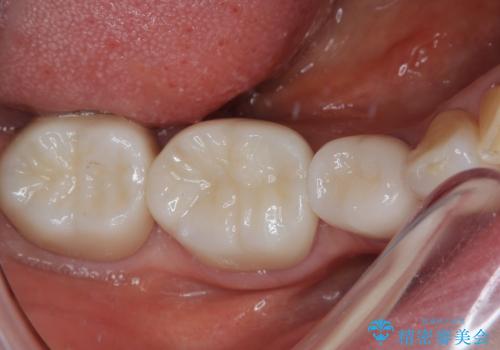

奥歯の目立つ銀歯をセラミックに オールセラミッククラウン治療

長年口を開ける度に気になっていた銀歯が一気に自然な色合いとなり、患者様には大変満足していただけました。